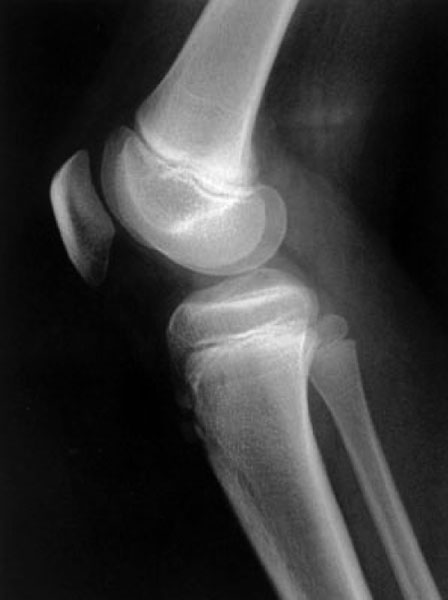

次の文により9・10の問いに答えよ.10歳の女児.1か月ほど前から運動後に膝の痛みを訴え,膝脛骨結節部に圧痛があった.単純エックス線写真を下に示す.最も考えられるのはどれか.

• 5.Osgood-Schlatter病

解答: 5